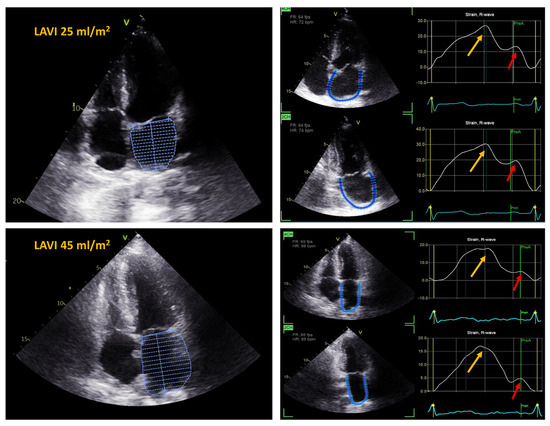

| LAVI, mL∙m−2 (SD) | 37.9 (7.1) | 28.6 (4.8) | <0.001 |

| LA emptying fraction, % (SD) | 50.4 (6.5) | 60.8 (6) | <0.001 |

| PALS, % (SD) | 17.4 (4.7) | 26.5 (6.9) | <0.001 |

| PACS, % (SD) | 6.0 (4.5) | 14.8 (5.8) | <0.001 |